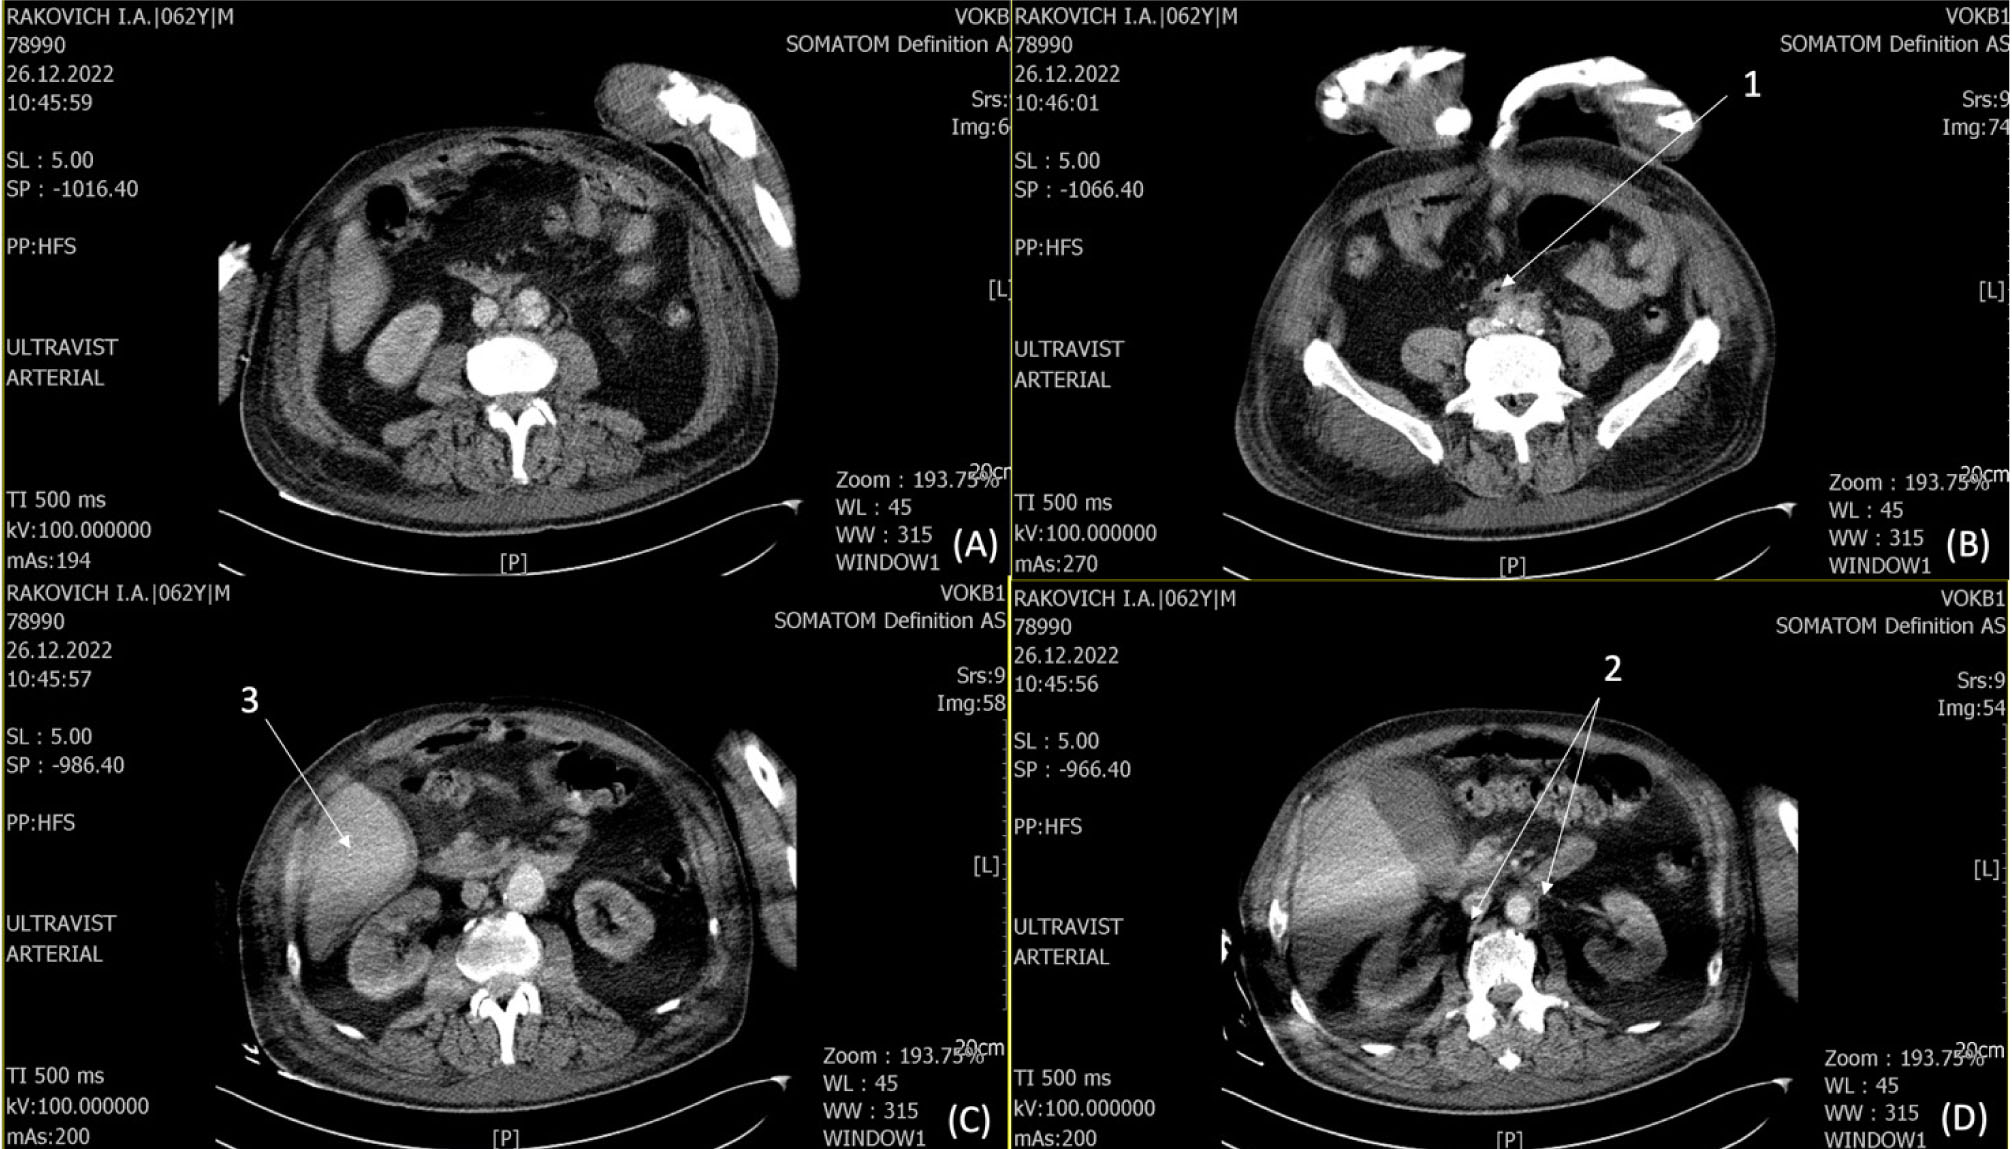

Пациент 62 лет поступил в ГБУЗ ВОКБ № 1 20.12.2022 г. в тяжелом состоянии, с жалобами на отек, распирающие боли в правой нижней конечности, периодические приступы повышения АД, температуры тела, одышку, общую слабость. В анамнезе от октября 2021 г. находился на стационарном лечении в хирургическом отделении ГБУЗ ВОКБ № 1 с подозрением на рецидивирующее ЖКК, при обследовании на ФГДС язв не обнаружено. При КТ брюшной полости с контрастированием выявлена аневризма брюшного отдела аорты с интимным прилеганием к стенке двенадцатиперстной кишки с подозрением на формирование свища (пузырьки воздуха в тромбомассах полости аневризмы). 10.11.2021 г. по решению консилиума проведено оперативное вмешательство: резекция аневризмы брюшного отдела аорты с аорто-подвоздошно-бифуркационным внутримешковым протезированием, ушивание дефекта стенки двенадцатиперстной кишки, наложение холецистостомы. Послеоперационный период без осложнений, дренаж из брюшной полости удален на 15-е сутки, пациент выписан в удовлетворительном состоянии. С начала октября 2022 г. стал отмечать боли в правом бедре, затем отметил уплотнение и чувство жара в бедре, боли усилились. 03.10.2022 г. обращение в приемный покой ГБУЗ ВОКБ № 1, выявлена и вскрыта флегмона правого бедра от 03.10.2022 г., с положительной динамикой пациент выписан для дальнейшего лечения по месту жительства. С начала декабря стал отмечать отек, распирающие боли в правой нижней конечности, периодическое повышение температуры тела. Операция: 21.12.2022 г. вскрытие абсцесса задней поверхности правого бедра. На УЗИ мягких тканей правой голени выявлено наличие свободного жидкостного компонента, в срочном порядке 23.12.2022 г. выполнено вскрытие флегмоны правой голени, санировано до 100 мл гнойного отделяемого. 26.12.2022 г. получен результат бак посева – E.coli 10 × 8, чувствительная к меропенему. По КТ брюшной полости и органов малого таза с контрастированием от 26.12.2022 г. – МСКТ картина локального расширения инфраренального отдела аорты. Отмечаются отдельные увеличенные параортальные лимфатические узлы. Воспалительные изменения в мягких тканях бедра (множественные абсцессы) (рис. 3).

Рис 3. КТ с контрастированием. 1, 2 – единичные пузырьки воздуха в парапротезной области; 3 – воспалительные изменения в мягких тканях бедра в зоне сканирования